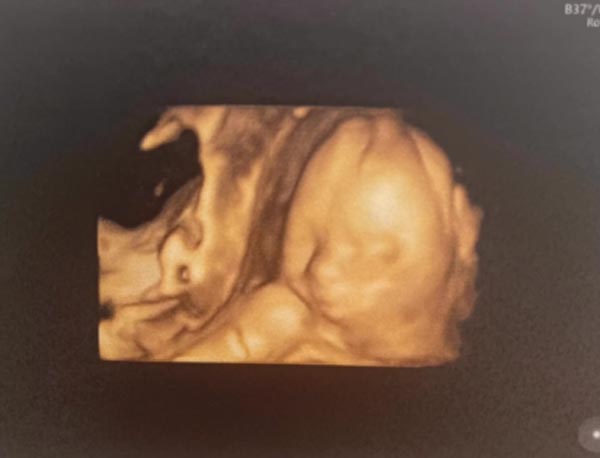

ล่าสุด (9 พฤศจิกายน 2565) สาวไอซ์ ก็ออกมาเผยภาพลูกสาวในท้องให้แฟน ๆ ได้ชมกันเป็นครั้งแรกหลังไปอัลตราซาวด์ 4 มิติมา พร้อมลงแคปชั่นว่า "ลุ้นหน้าลูกสาวจะออกทางเอเชียหรือออกสายฝอมากกว่ากันน้าาา"

โดยสาวไอซ์ก็เปิดใจว่า ตื่นเต้นมาก หน้าลูกสาวก็มาเต็ม มาครบ เป็นครั้งแรกที่ได้เห็นลูกชัด ๆ ว่าหน้าตาเขาจะเป็นแบบนี้ แต่ออกมาก็คงไม่ได้เป๊ะขนาดนั้น และขอบคุณทุกคนที่เข้ามาแนะนำว่าเป็นคุณแม่ต้องเตรียมตัวยังไงบ้าง ส่วนที่ก่อนหน้านี้ดูเหมือนท้องไม่ใหญ่ แต่ตอนนี้เข้าเดือนที่ 8 ท้องก็มาเลย ขยายเร็วมาก คุณหมอก็บอกว่าลูกพัฒนาการดี ตัวใหญ่กว่าเกณฑ์ด้วย ซึ่งอาจจะเป็นเพราะเขาเป็นลูกครึ่งด้วย